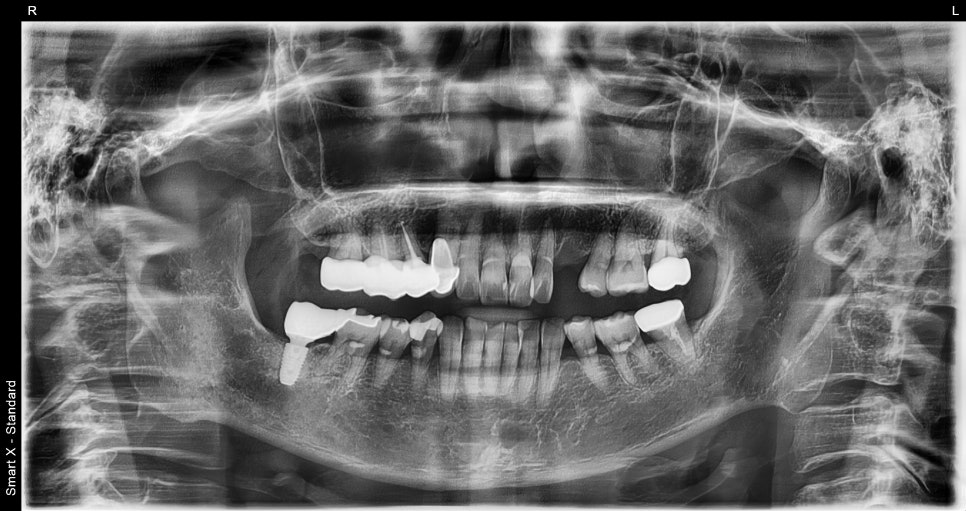

📸 Panoramic X-ray

Initial X-ray of the osteomyelitis patient